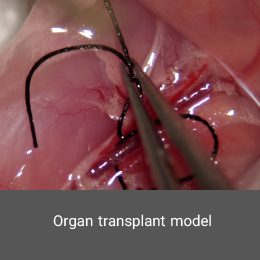

- Surgery and biopsy

- Create and induce a variety of animal models